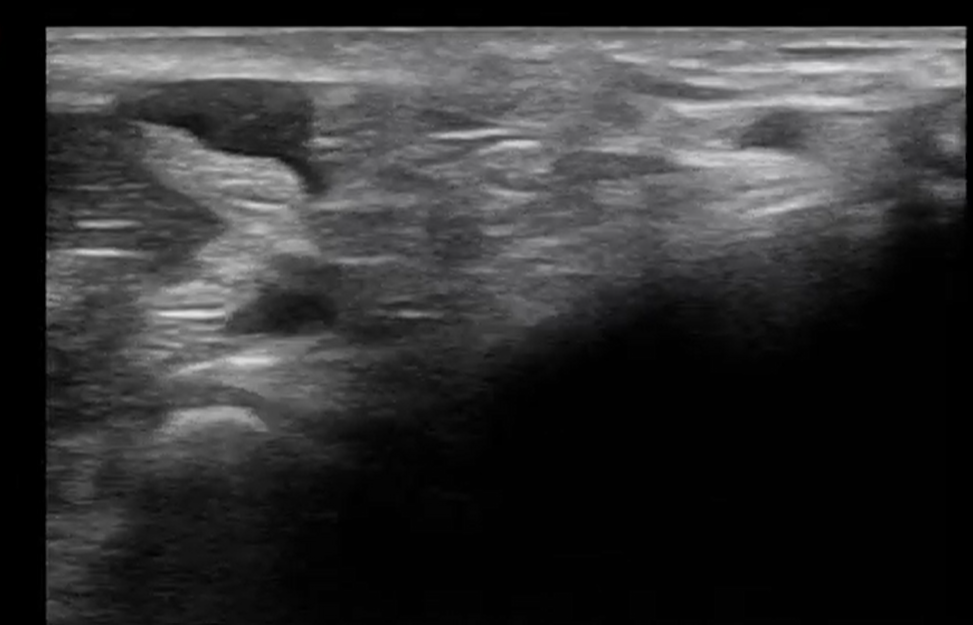

Mujer de 28 años, con AP de Ehlers-Danlos y asma. Hace 2 días acudió a Urgencias por proceso infeccioso respiratorio donde le solicitaron una gasometría arterial radial como parte del estudio. Desde entonces, la paciente refiere parestesias en territorio del nervio mediano con determinadas posturas. En la exploración física: hematoma visible sobre la arteria radial, sin déficit motor ni pérdida de fuerza. Parestesias desencadenadas con la flexión palmar y extensión forzada de la muñeca. Signos de Phalen y Tinel negativos. Integramos la ecografía clínica como parte de la exploración para evaluar en tiempo real la relación anatómica entre el hematoma y el nervio mediano, descartar otras patologías graves y orientar la toma de decisiones.

Hallazgos ecográficos

Se identificó un hematoma localizado justo por debajo del nervio mediano, que con la flexoextensión de la muñeca provocaba su compresión. No se realizaron pruebas adicionales. La ecografía clínica fue suficiente para el diagnóstico y manejo.

Hematoma postpunción con compresión dinámica del nervio mediano.

A los 15 días, la paciente refería clara mejoría. La ecografía de control mostró desaparición del hematoma y normalización del área transversal del nervio mediano (9 mm²).